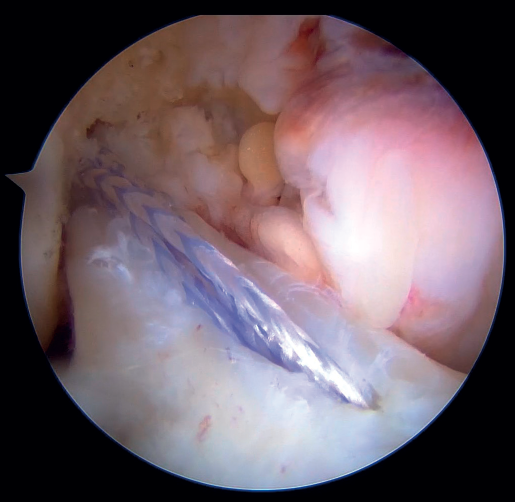

Once a good view of the central compartment is obtained, the area of the femoral footprint of the ACL is prepared to leave exposed bone, and microperforations are made in the medial wall of the lateral condyle to leave a bleeding bed to favor healing of the ligament (Figure 3). These microperforations can be made using specific instruments or with the implant punch. The advantage of using the punch is that the implant insertion site can be prepared at the same time, and only one instrument is used for the entire process (Figure 4). This step can be done after the suture has been prepared in the ligament, although doing it beforehand avoids the threads from standing in the way. The ideal point for fixation is just anterior to the native ACL footprint, although if the tear is partial or corresponds to Sherman I, it can be taken to the anatomical footprint without difficulty.

The anteromedial and posterolateral fascicles of the ACL are then identified for suturing separately. Using a suture passer, a closed loop suture is passed through the anteromedial fascicle at its most distal zone, and the loopless extremity is carried alternately (medial to lateral, lateral to medial and so on) to the most proximal zone, usually involving 3 or 4 passes of the suture. The thread may knot on itself during suturing if we are not attentive to it on entry and exit. To solve this problem, we simply undo the knot with retrieval forceps and repeat the step if necessary.

On completion, the thread is retrieved through the accessory anteromedial portal. The process is then repeated, this time with the posterolateral fascicle. To prevent the first thread from breaking with passage of the second thread, it must be ensured that entry and exit in the ligament are very posterior and ideally somewhat proximal to those used for the anteromedial fascicle. Once having reached the most proximal zone after 3 or 4 passes, retrieval is carried out in the same way through the accessory anteromedial portal.

Outside the knee, the threads are loaded into a knotless anchor implant with a tape that will act as anterior reinforcement of the ACL when attached to the tibia. Once the implant has been loaded, it is inserted into the previously prepared site. This step is facilitated when viewing is made from the anteromedial portal, as it affords a better perspective of the zone (Figure 5). Once the implant has been inserted, the suture threads are cut at the level of the condylar wall.